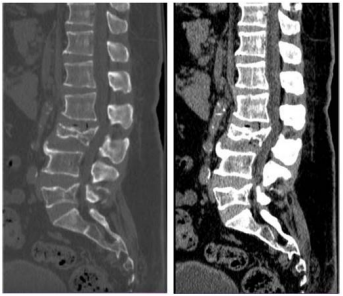

Um paciente de 62 anos de idade foi vítima de queda da própria altura há cerca de três horas. Ele chegou ao pronto-socorro queixando-se de dor lombar de moderada intensidade.

No caso descrito, foi solicitada uma TC da coluna lombar, conforme apresentado. Esse exame mostra fratura de